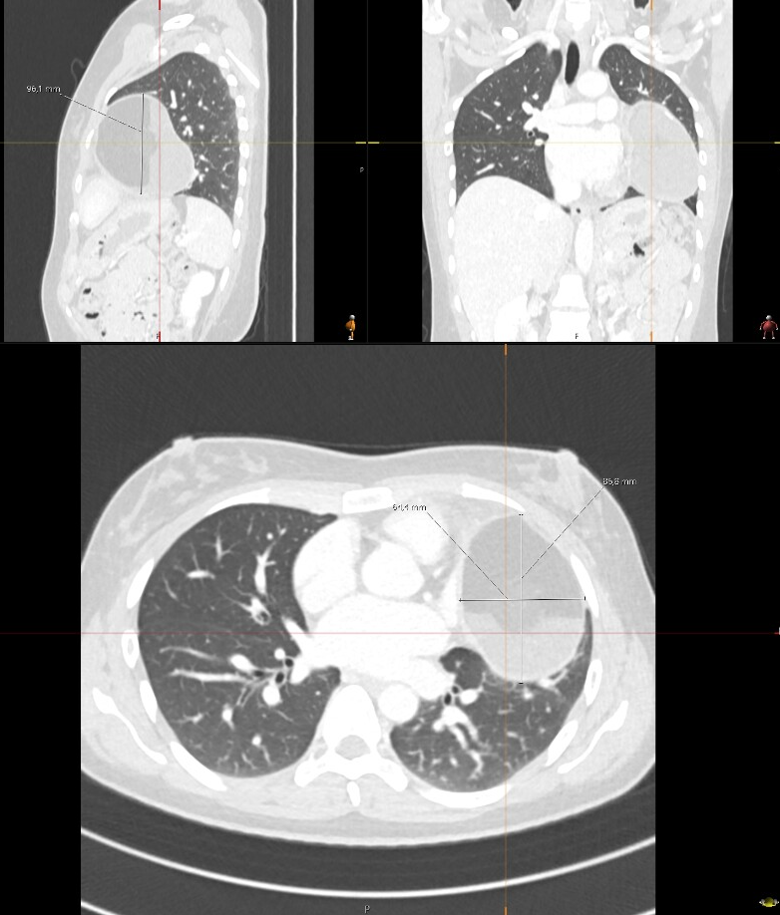

Beeldvorming – aanwijzingen op X-thorax, CT of MRI

• Massa in het voorste mediastinum (anterieur van trachea en grote vaten).

• Grote (>3 cm), slecht afgrensbare of inhomogene massa.

• Vasculaire compressie of vervaging van grens met omliggende structuren.

• Lymfadenopathie, pleuravocht of pericardvocht.

• Invasie in pericard, long, sternum of grote vaten.